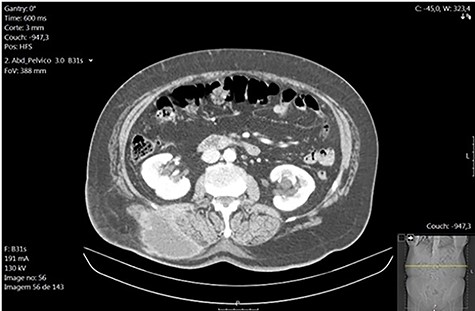

A 79-year-old woman presented in the emergency department with a painful right lumbar mass which had been increasing over the previous month. She denied fever, gastrointestinal and urinary symptoms or any recent trauma. Physical examination revealed a 10-cm long tender right lumbar lump with inflammatory signs suggesting to be an abscess. Laboratory investigations revealed a normal white blood cell count (9100/μl; segmented neutrophils, 68.0%), a hemoglobin level of 14.24 g/dl, an elevated C-reactive protein level (5.70 mg/dl) and normal hepatic and renal biochemical parameters. Computed tomography was performed which detected a well-defined collection of the subcutaneous tissue with 8.2 × 5.3 × 6.8 cm, with no retroperitoneal extension or renal involvement (Fig. 1). The patient had no relevant past medical history besides an elective laparoscopic cholecystectomy for symptomatic gallstones 3 years earlier. The operative report documented the procedure as ordinary except for gallbladder perforation with spillage of bile and gallstones into the peritoneum. No early or late complications were associated with the procedure and the anatomopathological examination showed chronic cholecystitis. A provisional diagnosis of a right lumbar subcutaneous abscess requiring surgical drainage was initially made and the patient was taken to the operating theater to go through the procedure. Under general anesthesia, an incision over the lump was performed with immediate pus output confirming the diagnosis. During saline lavage of the cavity, a 5-mm solid greenish foreign body was detected, suspected to be a gallstone (Fig. 2). The patient was discharged on postoperative day 2 on oral antibiotics. The anatomopathological examination of the foreign body confirmed to be a gallstone and follow-up within a year was uneventful.